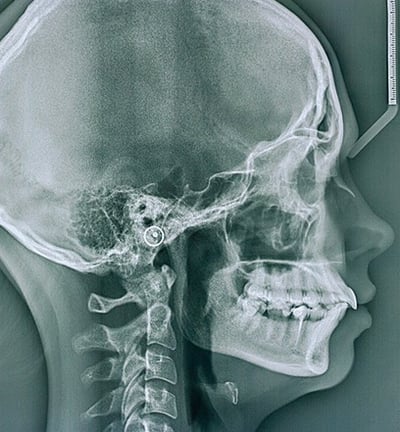

Téléradiographie de profil :